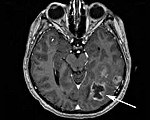

C79.3 Вторичное злокачественное новообразование головного мозга и мозговых оболочек